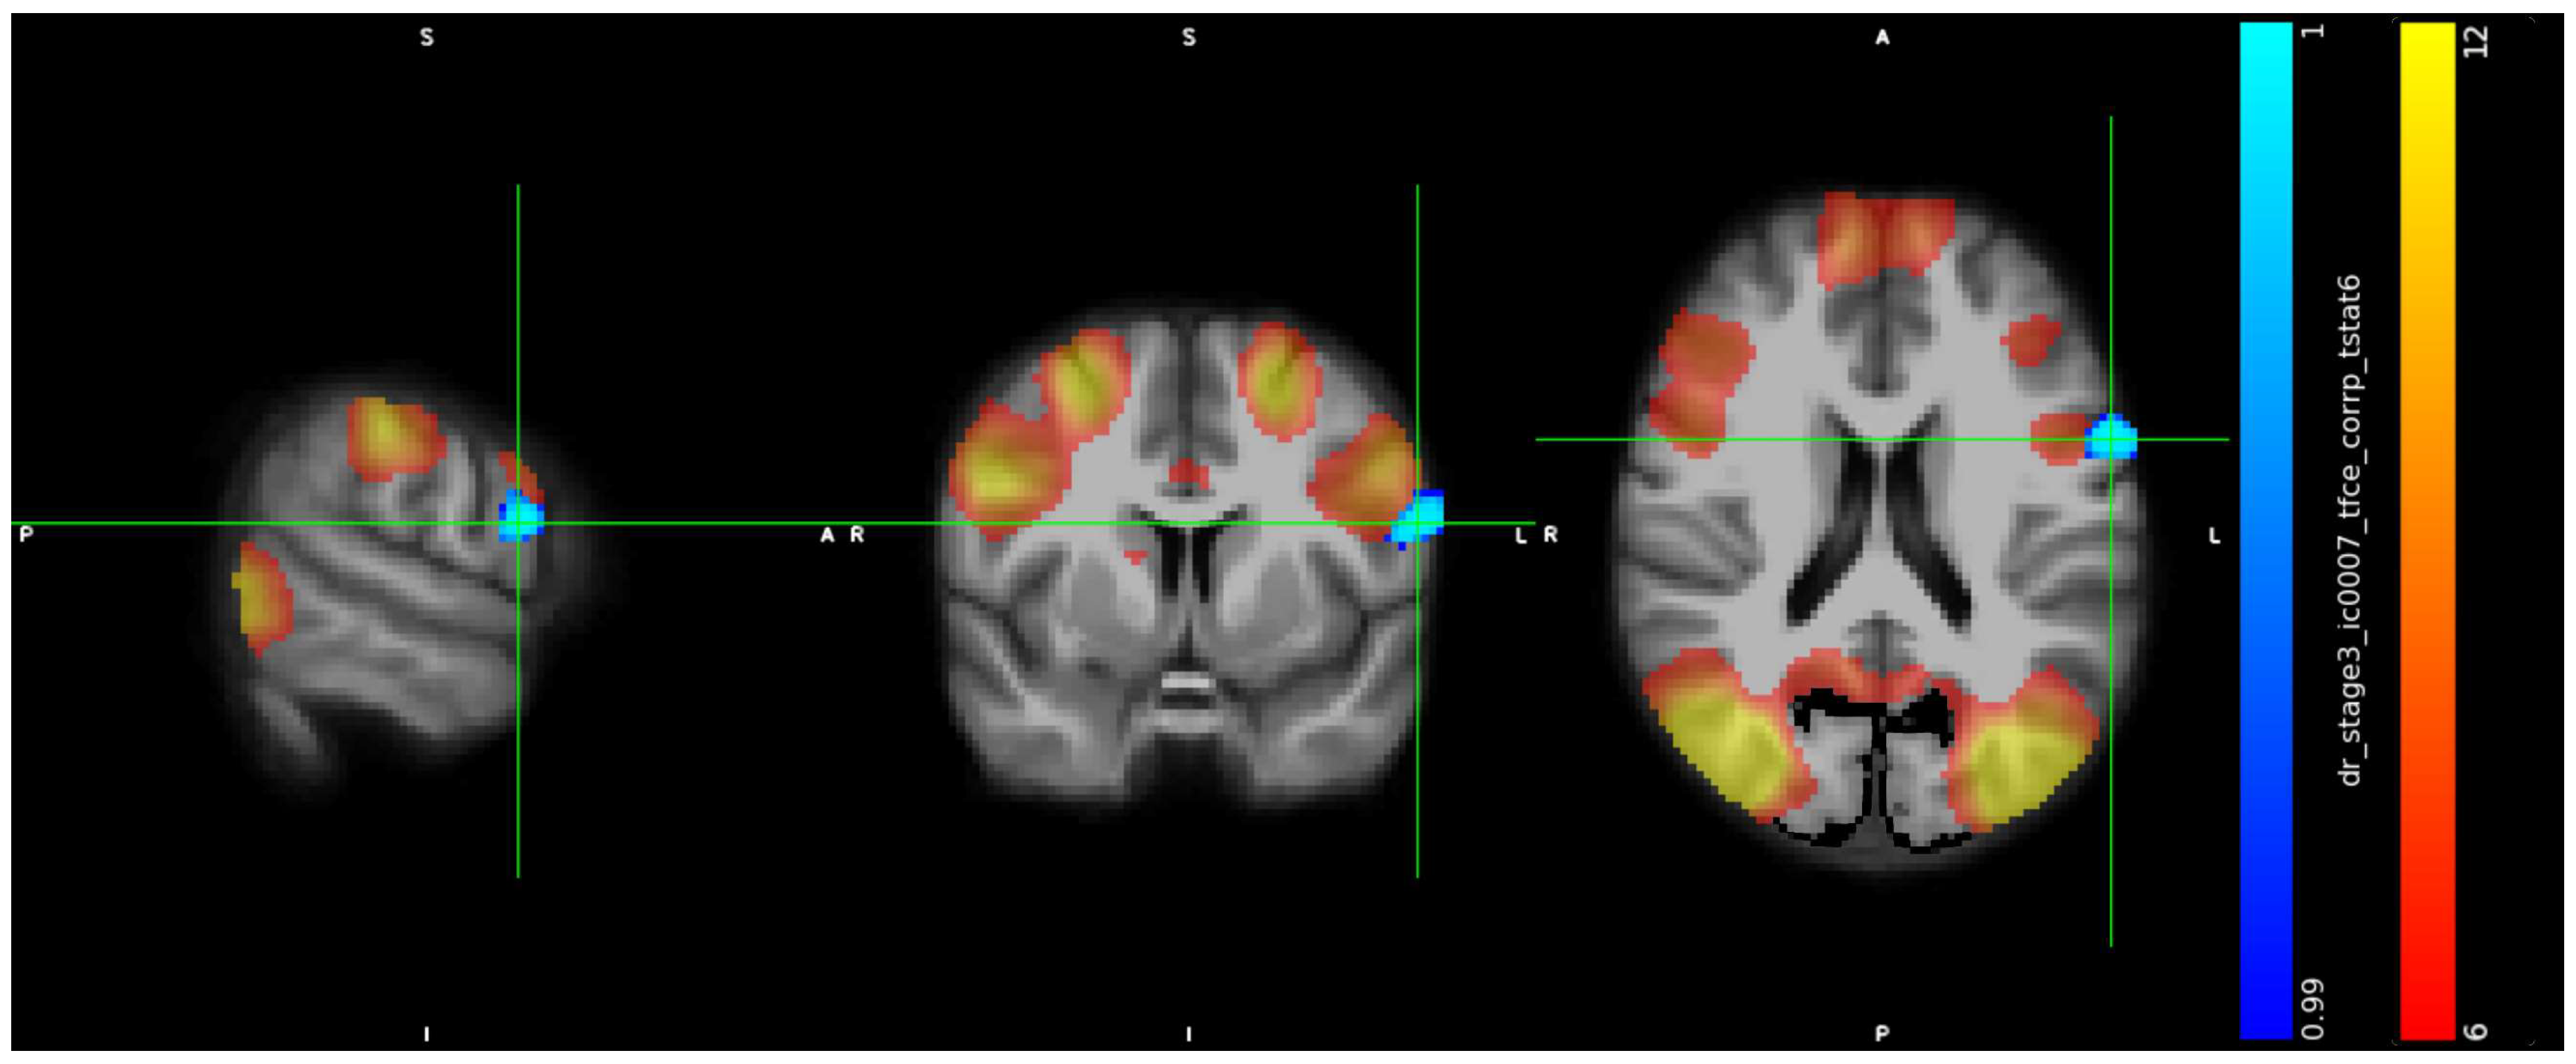

3.2. IC Analysis and Dual Regression